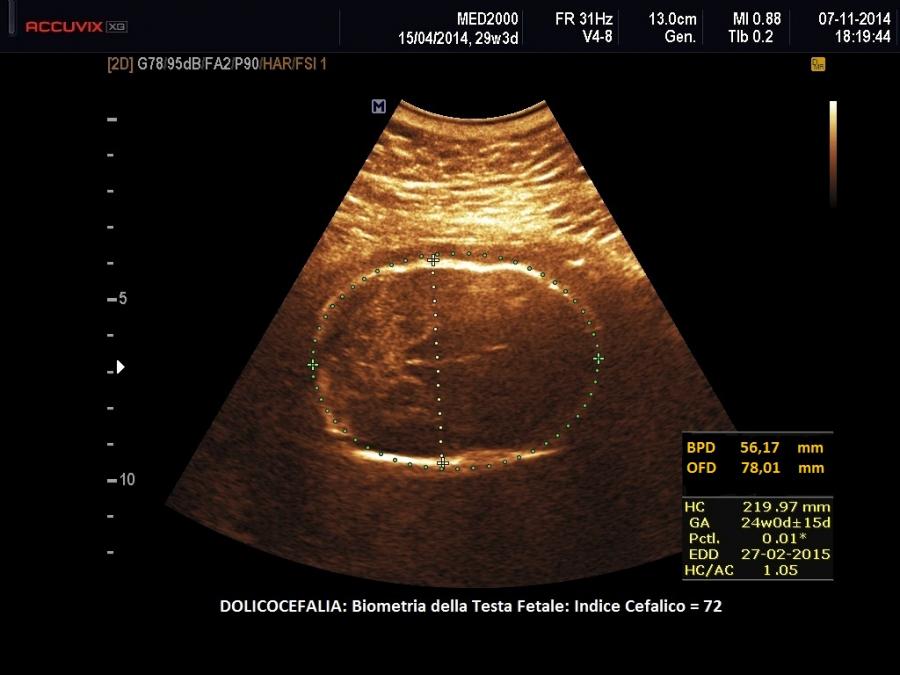

Dolicocefalia

La dolicocefalia è caratterizzata da una forma allungata del cranio per aumento del diametro antero-posteriore su quello trasverso.

La conformazione del cranio viene classificata in base all'Indice Cefalico; esso è dato dal rapporto percentuale tra diametro trasverso e diametro antero-posteriore del cranio.  In base a tale indice il cranio viene distinto in:

• dolicocefalico:  IC  <  76

• mesocefalico:   IC >= 76 < 81

• brachicefalico:  IC >= 81